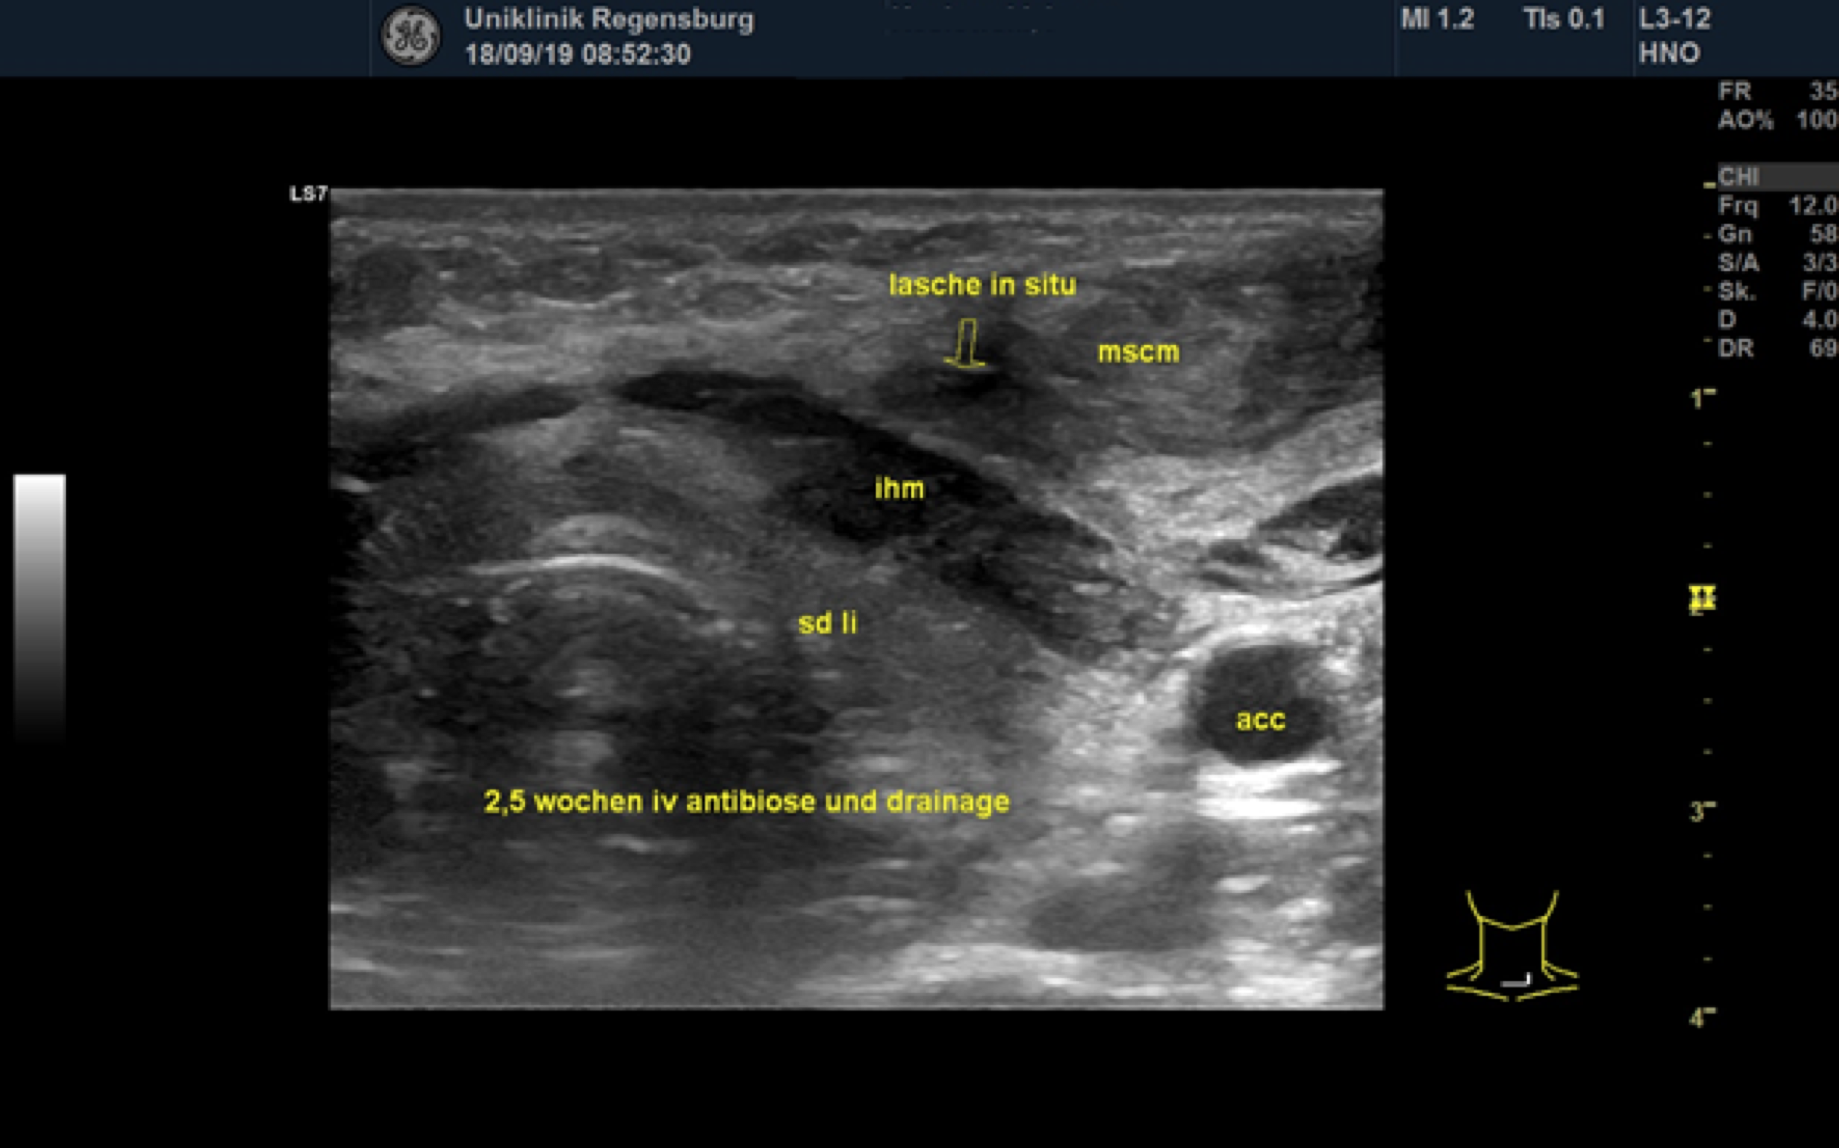

Sonographic check 2.5 weeks after start of treatment

Figure 7. Status after 2,5 weeks of i.v. antibiotic therapy and drainage. The fluid formation in the left thyroid lobe (sd li) has resolved. The infrahyoid muscle (ihm) and the sternocleidomastoid muscle (mscm) are still mildly thickened. The drain is still in place (lasche in situ). acc = Common carotid artery.

The patient received intravenous antibiotic therapy with amoxicillin /clavulonic acid for 3 weeks. During the course, a MRI of the neck was performed, which showed residual fluid in the former abscess cavity and another fluid collection in the left thyroid lobe, which appeared to be in contact. (Fig. 5) A sonographic check showed an echo-poor area around the left thyroid lobe corresponding to the MRI findings (Fig. 6). Owing to these findings and continued secretions from the wound area, revision surgery with wound drainage was carried out. Healing and improvement was confirmed on a subsequent sonographic check. (Fig. 7)